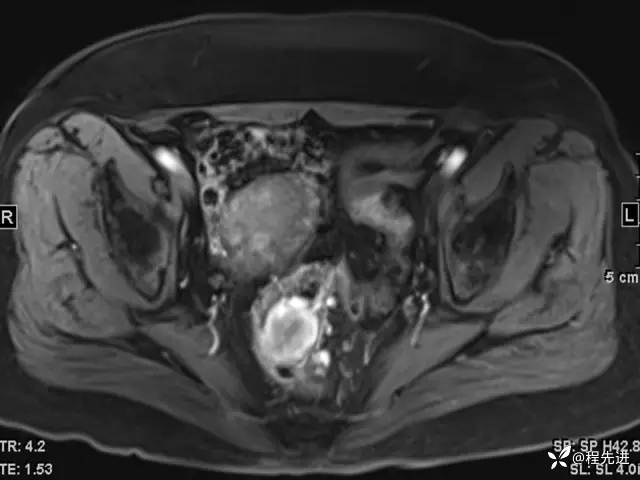

DWI、ADC:

T1增强: